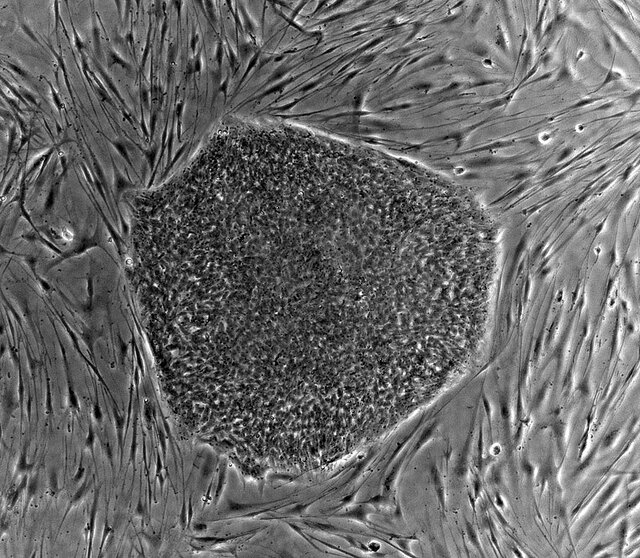

اندرامی با اشاره به اینکه در همین راستا «ریحانه نصیری منصور»، دکتری تخصصی مهندسی بافت، در طراحی و اجرای طرح تحقیقاتی حاضر بوده تا کار تحقیقاتی انجام شود، اظهار کرد: در این پژوهش توانستیم با طراحی یک پروتکل تمایزی بهینه شده با پلاسمای غنی از پلاکت، شبه جزایر لانگرهانس پانکراس را در آزمایشگاه تولید کنیم.

دکترای تخصصی بیوتکنولوژی پزشکی مازندران با تاکید بر ویژگیها و نوآوریهای مربوط به این پژوهش فناورانه گفت: در این پژوهش برای اولین بار، با یک پروتکل بهینه شده با پلاسمای غنی از پلاکت و با استفاده از سلولهای بنیادی با منشا خون قاعدگی، سلولهای شبه بتا انسولینساز پانکراس تولید شد که به غلظتهای مختلف از قند گلوکز پاسخ میدهند.